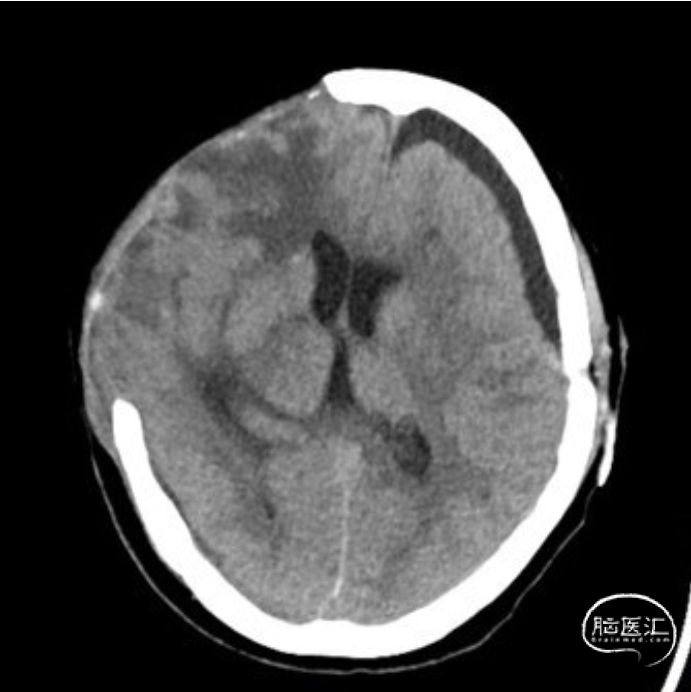

第一次实验:开放腰大池引流管,关闭左侧硬膜下引流管,操作后患者意识逐渐变差复查头颅CT:左侧硬膜下积液开始增多。实验暂停,重新开放硬膜下引流管。

重新开放左侧硬膜下引流管,同时保持腰大池引流管通畅,患者意识恢复至清醒状态,复查头颅CT:硬膜下积液明显减少,中线回归,颅内压力明显降低。

第二次实验再次关闭左侧硬膜下引流,保持腰大池引流开放,患者意识变差,再次转入嗜睡,复查头颅CT提示左侧硬膜下积液增多。

再次开放左侧硬膜下引流后患者意识好转,第三次实验保持左侧硬膜下引流通畅,关闭腰大池引流,操作后患者病情稳定,复查头颅CT提示硬膜下积液减少,中线基本恢复。